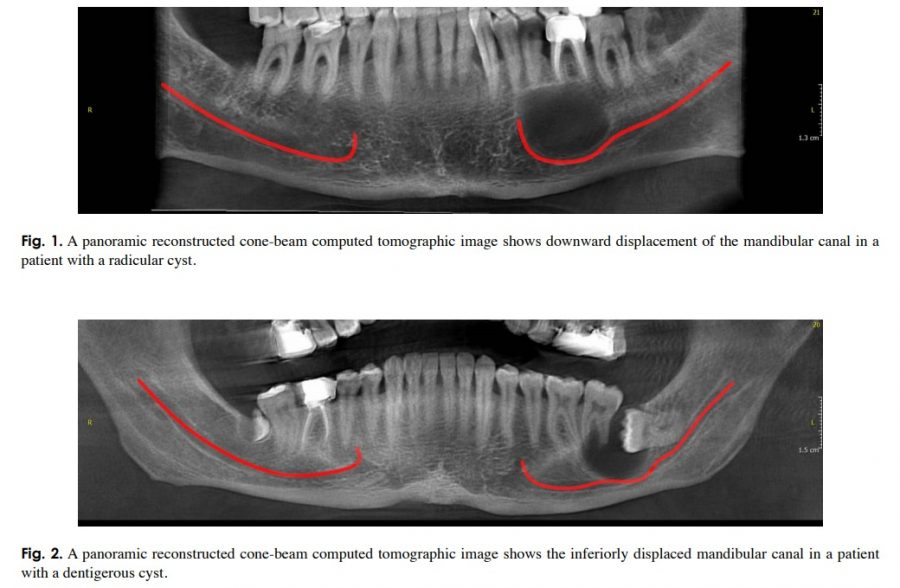

Common conditions associated with displacement of the inferior alveolar nerve canal: A radiographic diagnostic aid

Common conditions associated with displacement of the inferior alveolar nerve canal